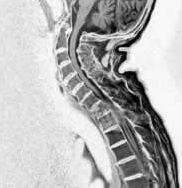

二.MIR檢查

對椎間盤突出、軟組織損傷及脊髓受累程度的判定意義較大,有條件者應爭取之。